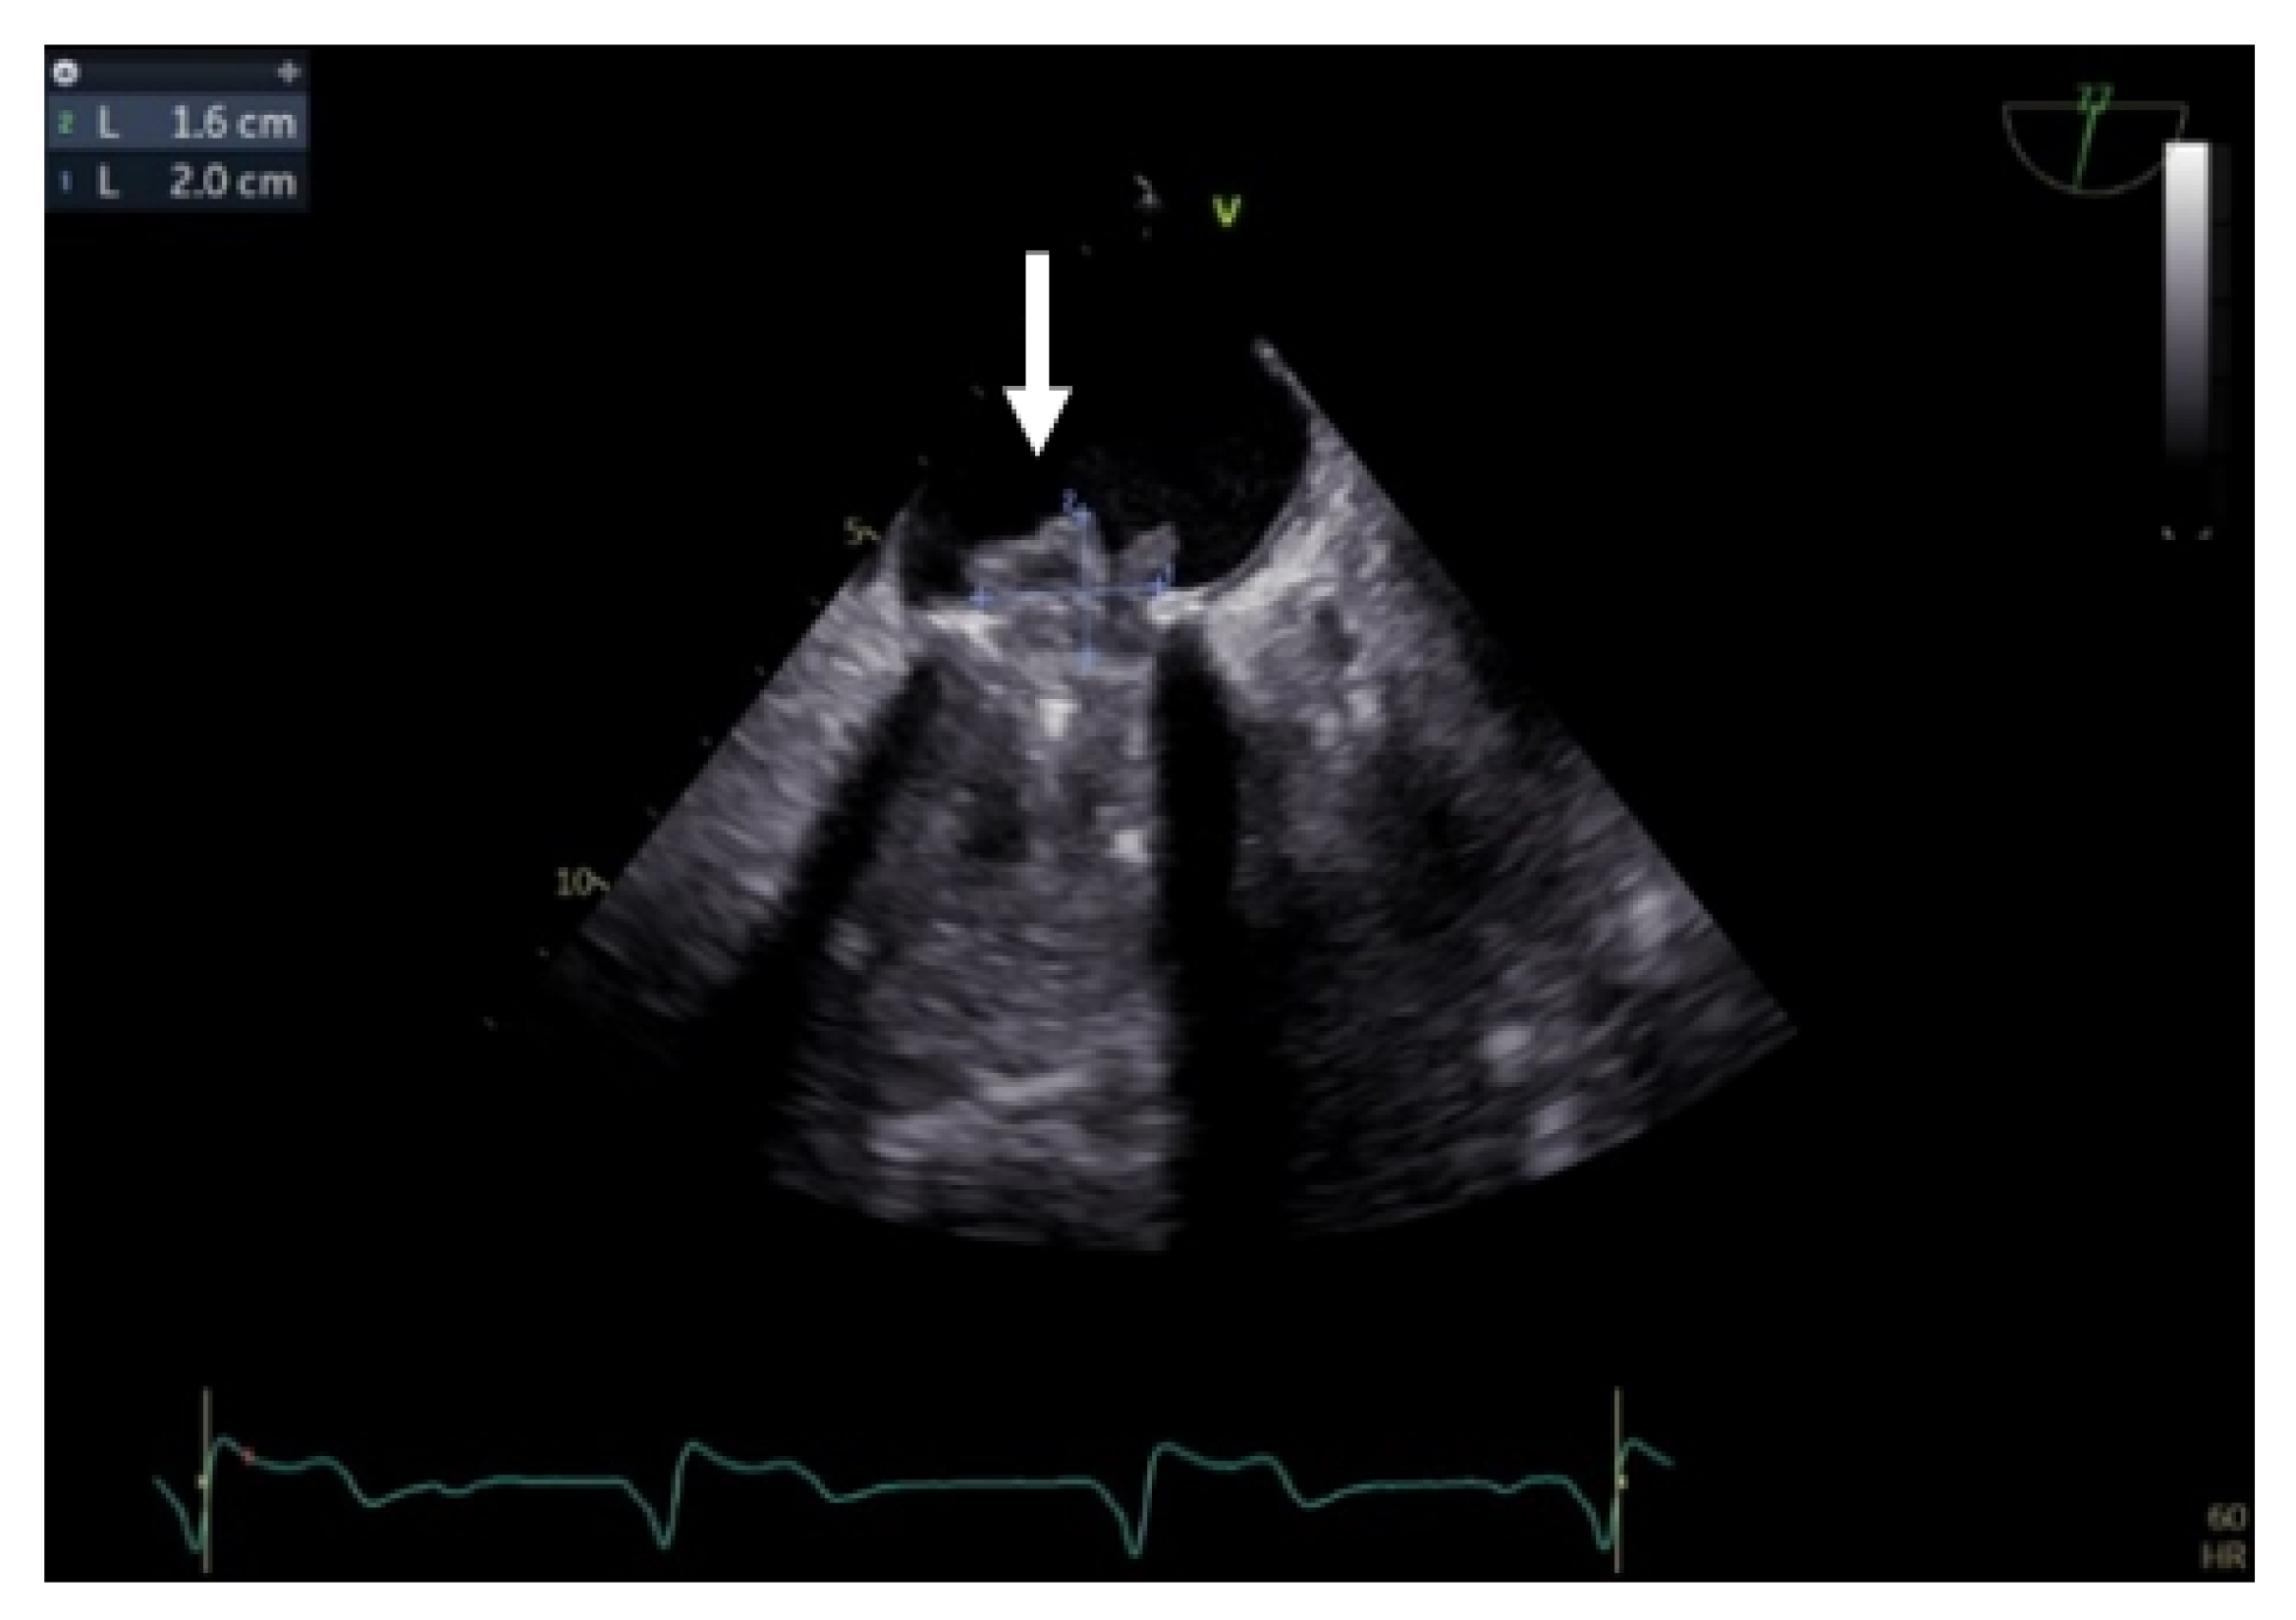

Despite the recognition that TEE is very effective in assessing mitral prostheses, it possesses limitations with regard to aortic prostheses due to the anterior position and acoustic shadowing of the prosthetic material, especially in bileaflet valves and when there is also a mechanical valve in the mitral position. The posterior part of the aortic prosthesis is well visualized, while the anterior part is shadowed by the reverberations determined by the disc. It can be challenging to see the thrombus in some situations, requiring the use of complementary imaging techniques such cinefluoroscopy and cardiac CT [24].

Transgastric and deep transgastric TEE views are helpful for measuring the transprosthetic gradients and LVOT diameter in order to calculate the effective area of the aortic prosthesis. Useful information is also obtained from the mid-esophageal view at 80°, where the prosthesis is visualised in a short-axis view (Figure 10). The mobility of the discs, the symmetry of their closing–opening, and the evaluation of intra- or paraprosthetic leaks are described [13]. Stress echocardiography could be beneficial in cases of uncertain diagnosis, where the assessment of the increased transprosthetic gradient is correlated with symptom reproduction. A significant increase in the gradient through the prosthesis suggests obstruction of the aortic prosthesis [13].

Figure 10.

TEE. Nonobstructive thrombus on the aortic prosthesis ring (arrow).